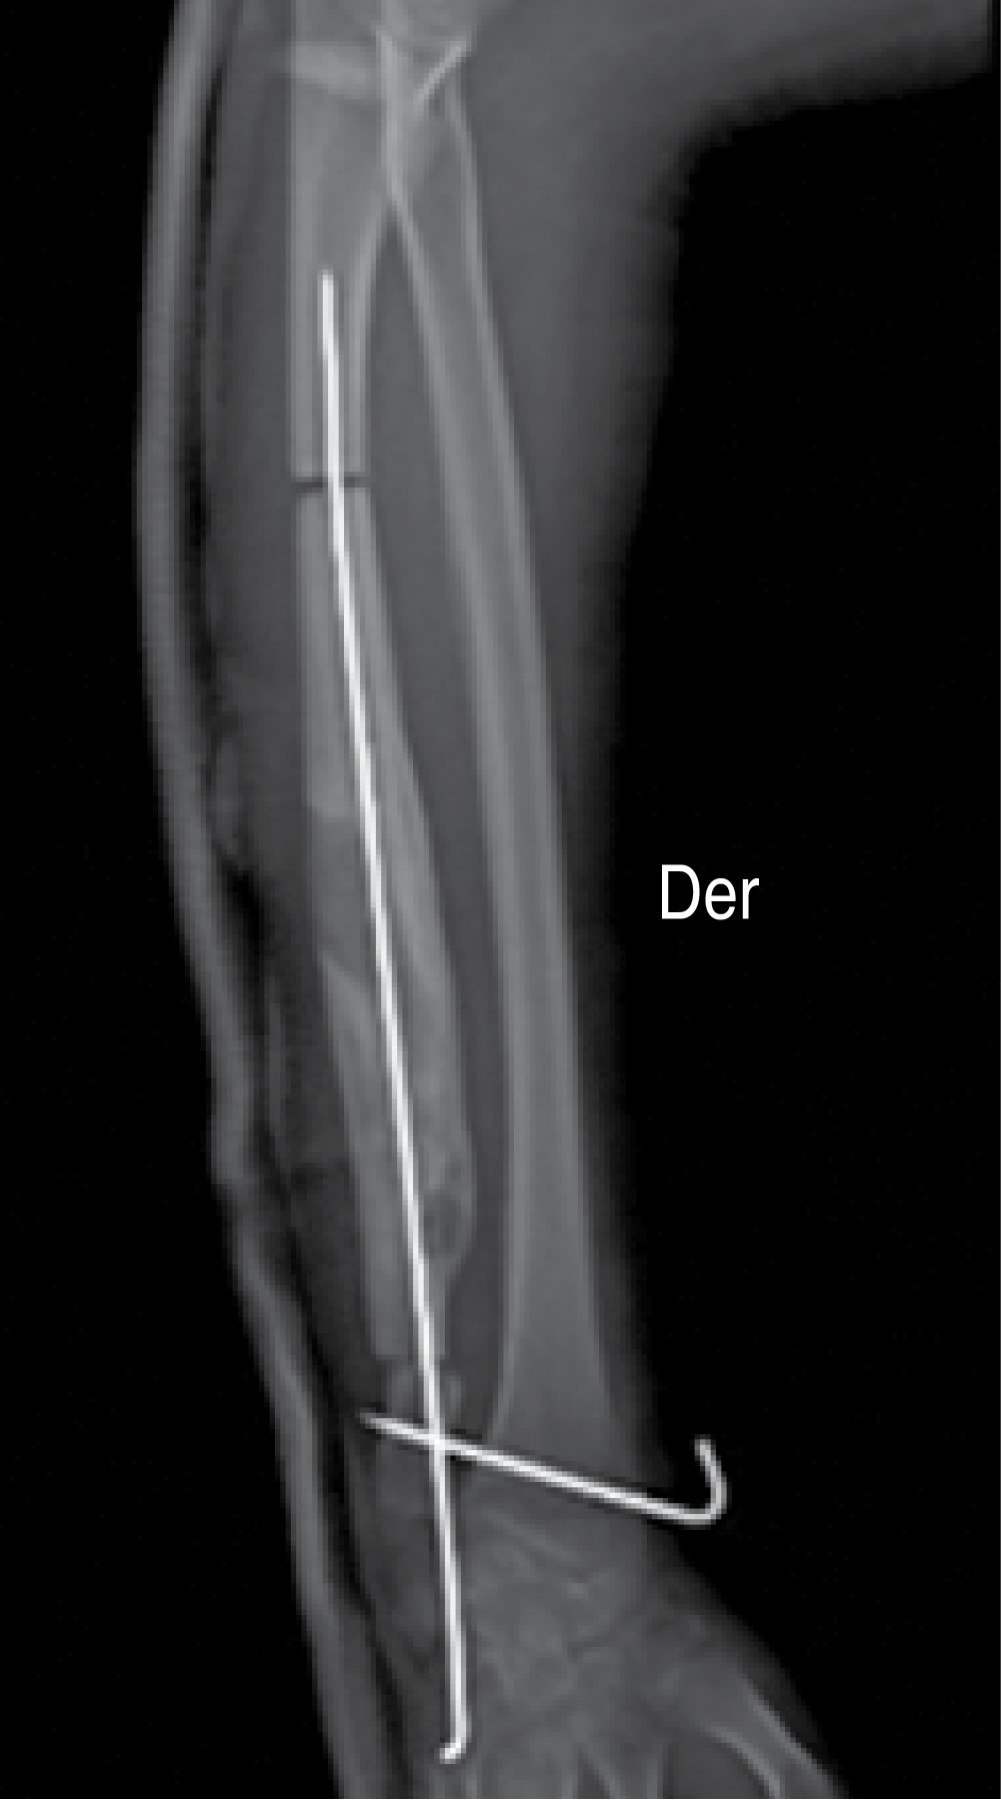

Figure 1

Figure 2

Figure 3

Figure 4

Figure 5

Figure 6

Figure 7

Figure 8